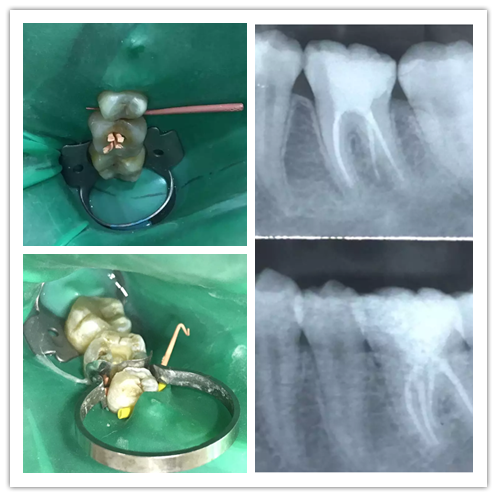

病例展示